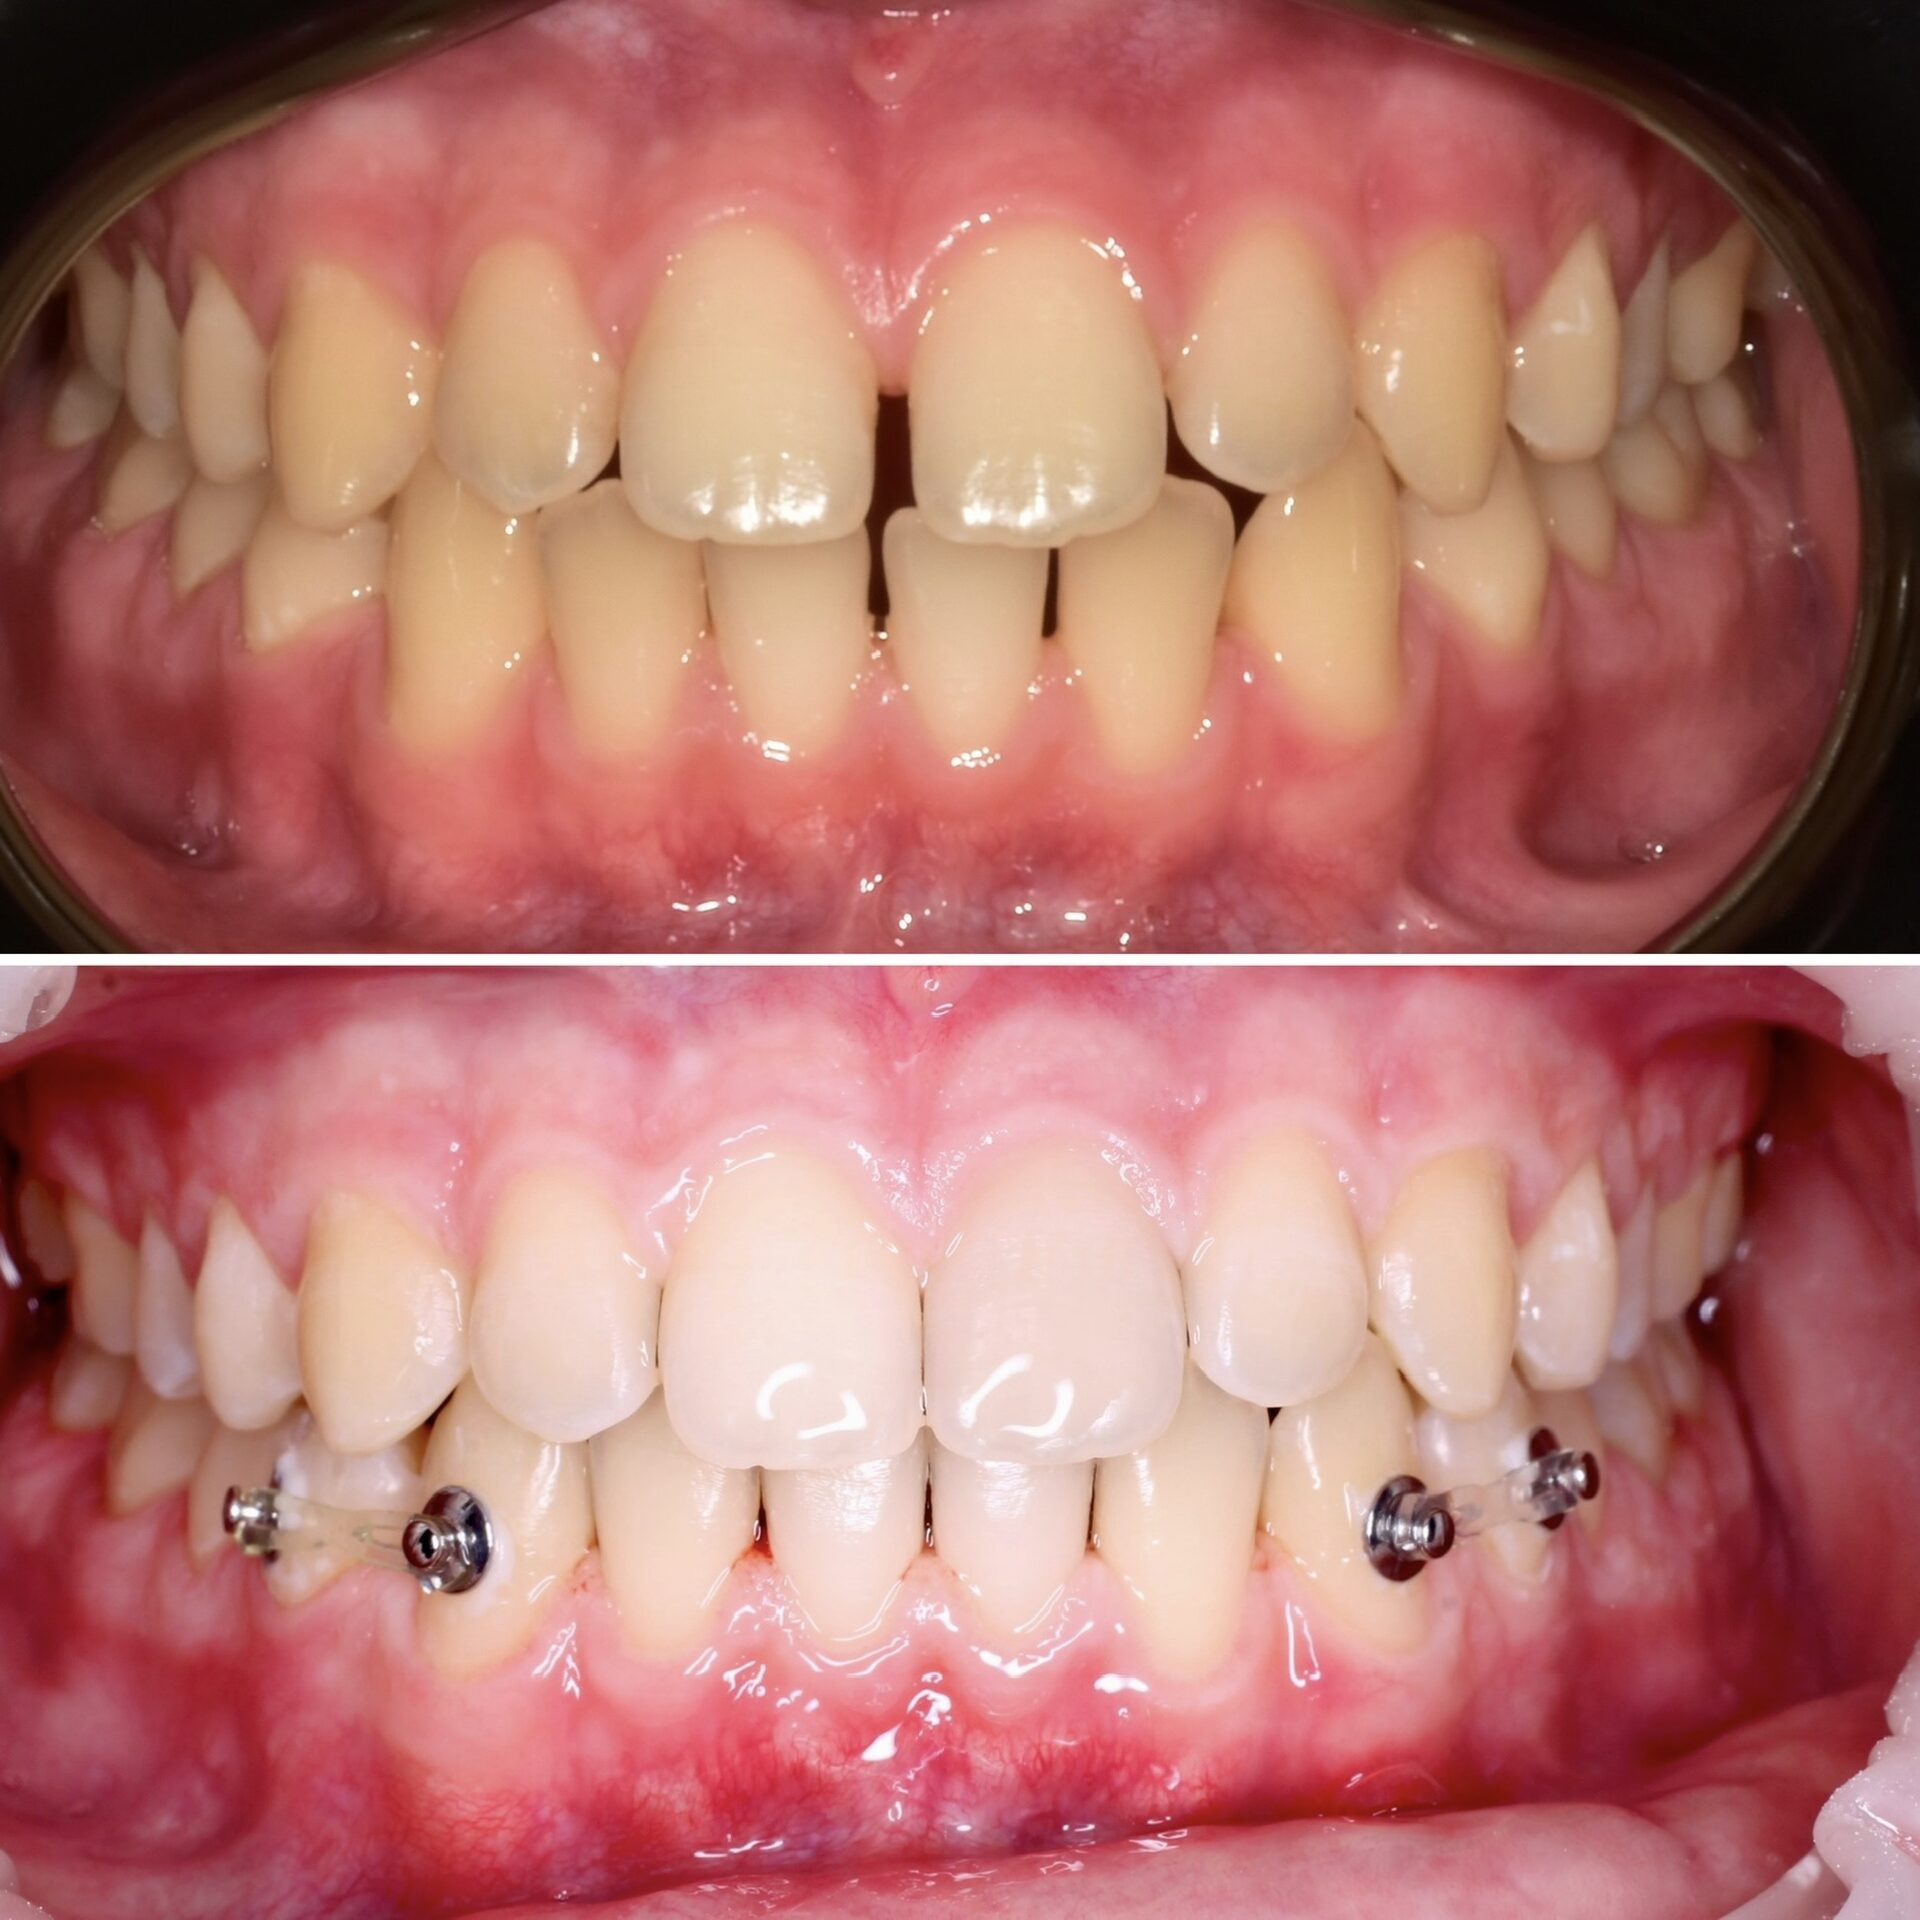

Виниры на своих зубах и коронки на имплантатах

Виниры на своих зубах и керамические коронки на имплантатах

Виниры на своих зубах,безметалловые коронки на имплантате